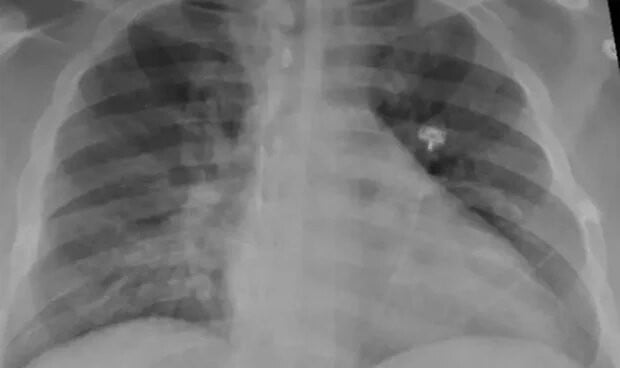

neumonía no diagnosticada en niños en el norte de China, pero no está claro si estos están asociados con el

aumento general de infecciones respiratorias informado anteriormente por las autoridades chinas o con eventos separados.

Programa de Monitoreo de Enfermedades Emergentes (ProMED), en varios hospitales de Beijing, la capital de China, junto con la provincia de Liaoning, se han desbordado los

niños con neumonía desconocida, provocando que las escuelas y las clases

se encuentren al borde de la suspensión.